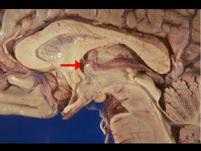

问题 如图箭头所示为大脑哪个部位 ( )

选项 A、穹窿 B、中脑导水管 C、后连合 D、室间孔 E、前连合 一、单项选择题

答案 D